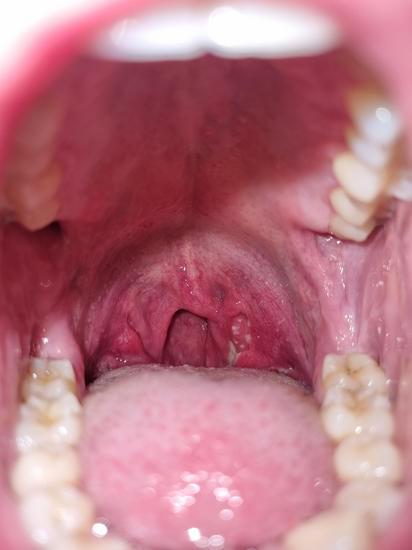

붓고 붉어진 편도: 편도가 붓고, 표면에 하얀 고름이 생기기도 합니다.